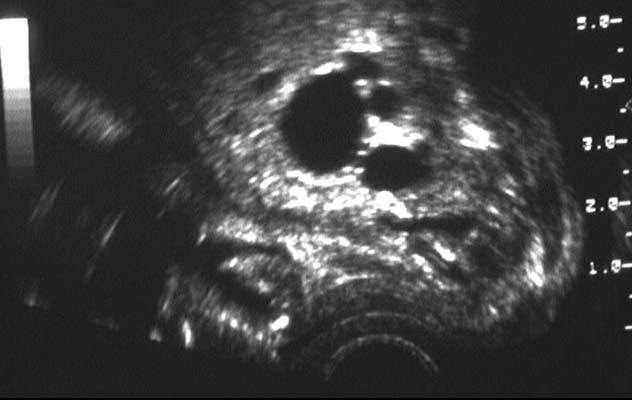

Hydronéphrose sur ectopie pelvienne